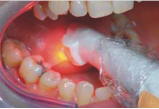

Přístroj na principu světlem aktivovaná desinfekce neboli fotodynamická antimikrobiální chemoterapie. Přístroj s okamžitým účinkem ničí veškeré mikroorganismy bez jakýchkoli vedlejších účinků. Jedná se o bezbolestné ošetření, které nevyžaduje anestezii, nemá vedlejší účinky a ničí 99% bakterií. Používá se především v parodontologii a implantologii při léčbě zánětů v okolí zubů a implantátů (dezinfekce tzv. chobotů), záchovné stomatologii (ošetření kazů) i endodoncii (dezinfekce kanálků zubu).